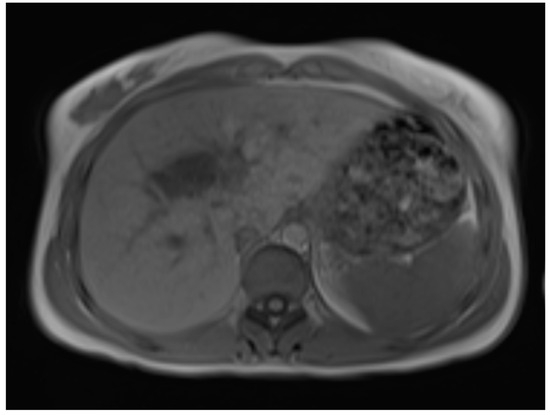

The surgical department decided not to opt for a surgical resection due to difficult access to the cyst, and therapy with the antihelminthic medication albendazole for four weeks was initiated. Additional diagnostics, including chest CT and an MRI scan of the brain, did not find any further extrahepatic manifestations of the hydatid disease. The chest CT scan included parts of the abdomen and also depicted the cyst and lower-attenuated daughter cysts (Figure 6).

Figure 6.

CT imaging shows a large hydatid cyst in segment IV, classified as WHO type CE2. The main cyst has slightly higher attenuation compared to the smaller peripheral daughter cyst.